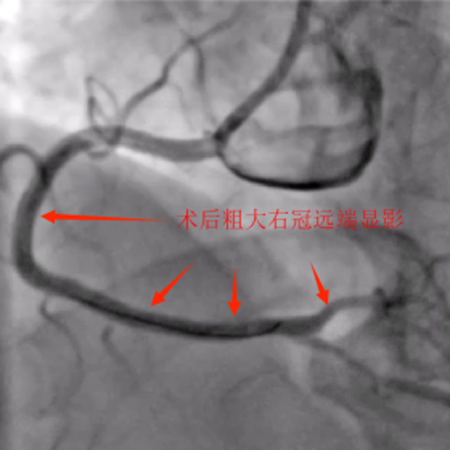

11月5日,患者各方面情况相对稳定,口服双联抗血小板聚集药物消化道反应也无异常。综合评估后再次为患者行冠脉介入治疗。术前我把老吴左右手都消毒了,左手备用,可能需要双侧造影辅助开通右冠。术中顺利开通右冠闭塞血管并植入支架恢复正常血流,同期解决前降支极重度狭窄病变并植入支架解除危机。手术总用时1小时40分钟,造影剂用量120ml,手术很顺利,比预想的效果要好,已经超预期完成。

12月3日,老吴第三次进入导管室,这次老吴很轻松,和我还有说有笑,而我却承受了比上次更大的压力,因为老吴是带着肯定而来,带着信任而来。结果左侧造影回旋支远端的同侧逆向供应血流消失了,不得不穿刺左手进行右冠造影为左冠回旋支导丝前进提供方向,皇天不负有心人,经过重重困难最终再次顺利开通了闭塞的回旋支,这一刻如释重负,汗水打湿了衣物,浸透了铅衣!